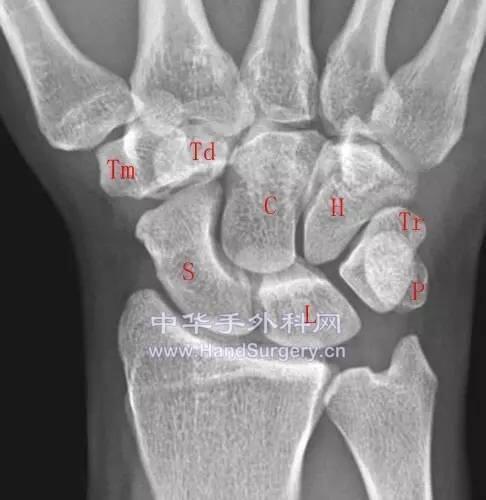

腕关节Gilula线

楼主| 发表于 2020-5-10 23:47:50 | 显示全部楼层

92750465_2.jpg

92750465_3.jpg